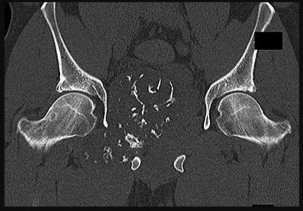

This patient has no known history of active malignancy. The radiograph shows a lesser trochanteric avulsion fracture (a fracture routinely associated with an underlying neoplasm). The bone scan reveals no other bone lesions. The femur fracture is statistically most likely to occur because of metastatic disease, but, without other evidence of metastasis, a primary bone sarcoma is possible, and biopsy is recommended before surgical fixation. Observation of this fracture, which is pathognomonic for neoplastic disease, is strongly discouraged.